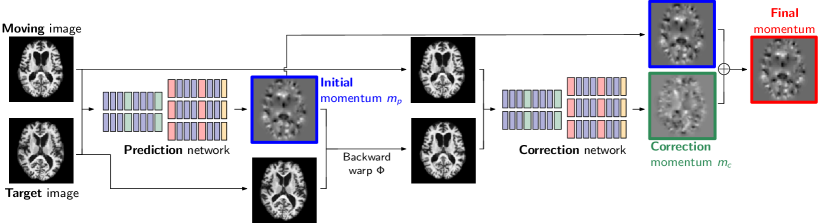

Our fast predictive simple geodesic regression approach is a combination of two methods: First, fast predictive image registration (FPIR) and, second, integration of FPIR with simple geodesic regression (SGR). Both FPIR and SGR are based on the shooting formulation of LDDMM [7]; Fig. 1 illustrates our overall approach. The individual components are described in the following.

2.3 Correction network

We follow [20] and use a two-step approach to improve overall prediction accuracy. An additional correction step, i.e., a correction network, corrects the prediction of the initial prediction network. Fig. 2 illustrates this two-step approach graphically. The correction network has the same structure as the prediction network. Only the inputs and outputs differ. For the prediction network, the inputs are the original moving image and the original target image; output is the predicted initial momentum. For the correction network, the inputs are the original moving image and the warped target image; the output is the momentum difference.